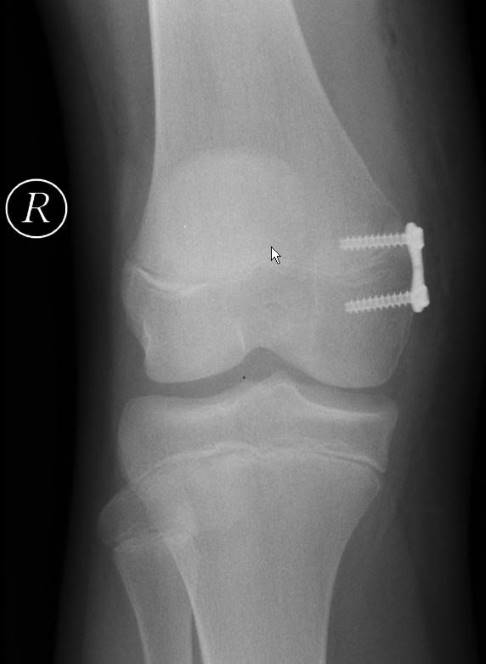

Im Wachstumsalter ist die temporäre Hemiepiphysiodese die erfolgversprechendste Methode zur operativen Begradigung der Beinachsen bei Kindern und Jugendlichen. Dabei wird die Wachstumsfuge im Bereich des Kniegelenks vorübergehend einseitig blockiert. Auf der anderen Seite bleibt die Wachstumsfuge weiterhin aktiv.

In einer minimalinvasiven Operation bringt der Orthopäde Implantate (z. B. Eight-Plate oder RigidTack) über kleinste Hautschnitte ins Kniegelenk ein. Über einen kleinen Draht wird das Implantat korrekt positioniert. Die Implantate werden außerhalb der Wachstumsfugen mit Titanschrauben im Knochen verankert und überbrücken diese. Es hängt vom Alter des Kindes und der genauen Beinachsenwinkel ab, welche Wachstumsfugen blockiert werden müssen.

Im weiteren Verlauf erfolgen alle 3 Monate klinische Kontrollen der Beinachsen, bis eine Begradigung bzw. minimale Überkorrektur eingetreten ist, damit keine erneute Fehlstellung entsteht (Rebound-Phänomen). Meistens ist dies nach ungefähr 10 bis 12 Monaten der Fall. Dann müssen die Implantate in einer weiteren minimalinvasiven Operation entfernt werden. Um eine häufige Strahlenbelastung durch Röntgen bei den Kontrollen zu vermeiden, kann eine Ganganalyse zur Beurteilung der statischen und dynamischen Beinachsen erfolgen.